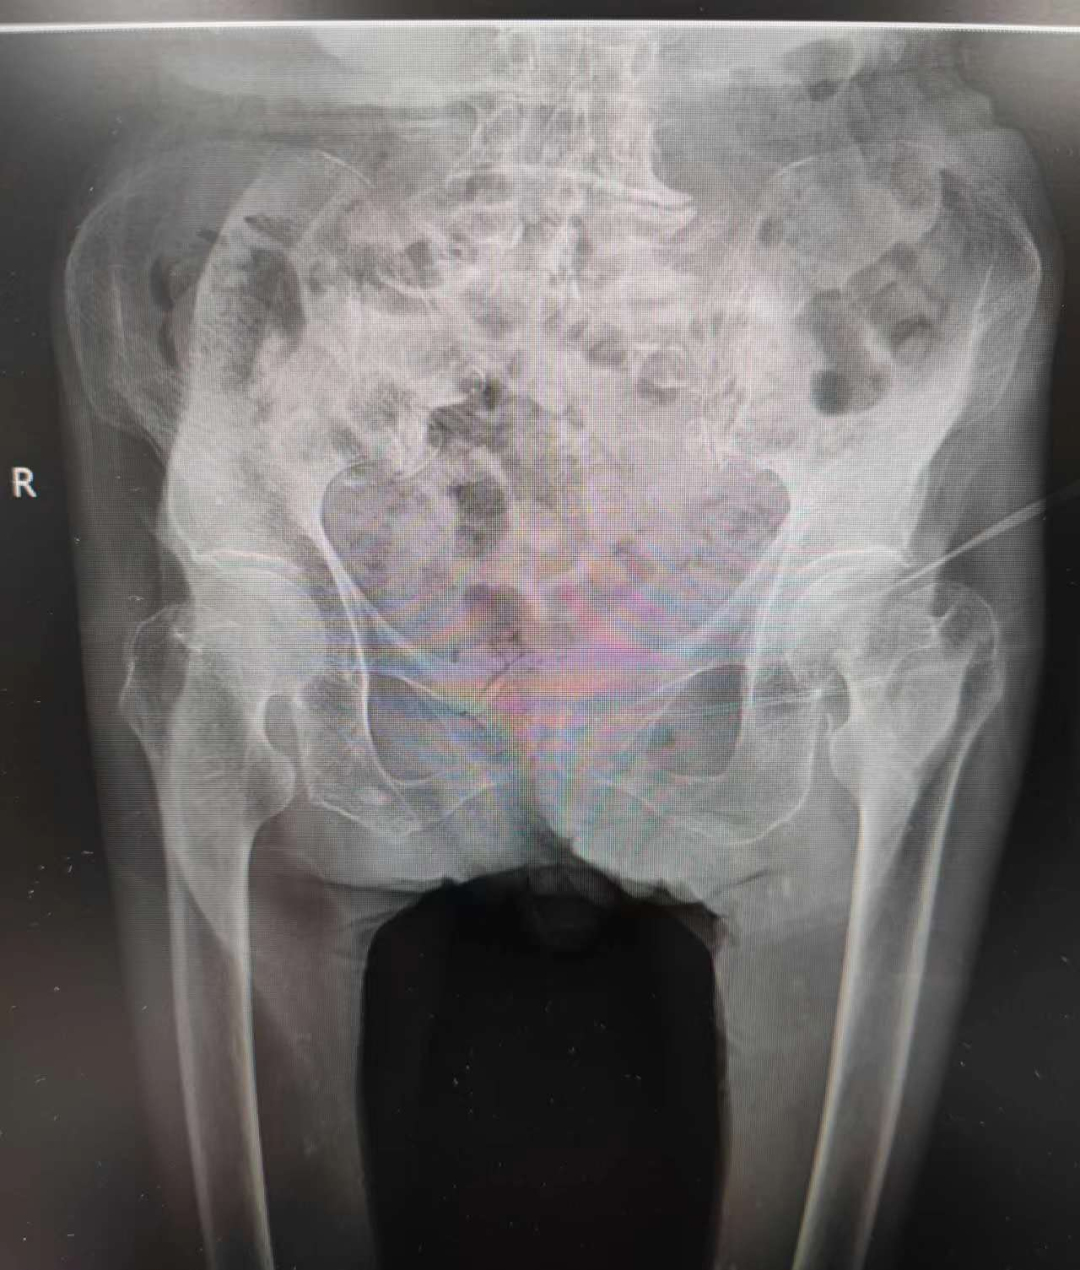

股骨颈骨折被称作“人生的最后一次骨折”。因为老年人摔倒发生股骨颈骨折的概率极高,且其并发症危害极大。预防髋部骨折并发症发生的最佳方式是早期手术治疗、术后早期的功能锻炼可大大降低并发症的发生。但由于老年患者年龄大,某些家属出于安全考虑会选择非手术保守治疗,殊不知非手术治疗同样存在并发症风险,会因长期卧床出现肺部感染,血栓,褥疮等。因此,对于股骨颈骨折老年患者而言,尽早手术,患者获益更大。

超高龄并不意味着手术“禁区”,随着我院在老年人髋部骨折治疗方面积累了丰富的经验及多学科协同发展的综合医疗水平不断提高,近年来已为很多高龄老人成功进行了手术治疗。对于高龄、超高龄老人骨折,我院专家认为应充分对患者进行综合评估后,尽早手术,恢复患者各项功能,减少卧床引起的并发症,降低死亡率。